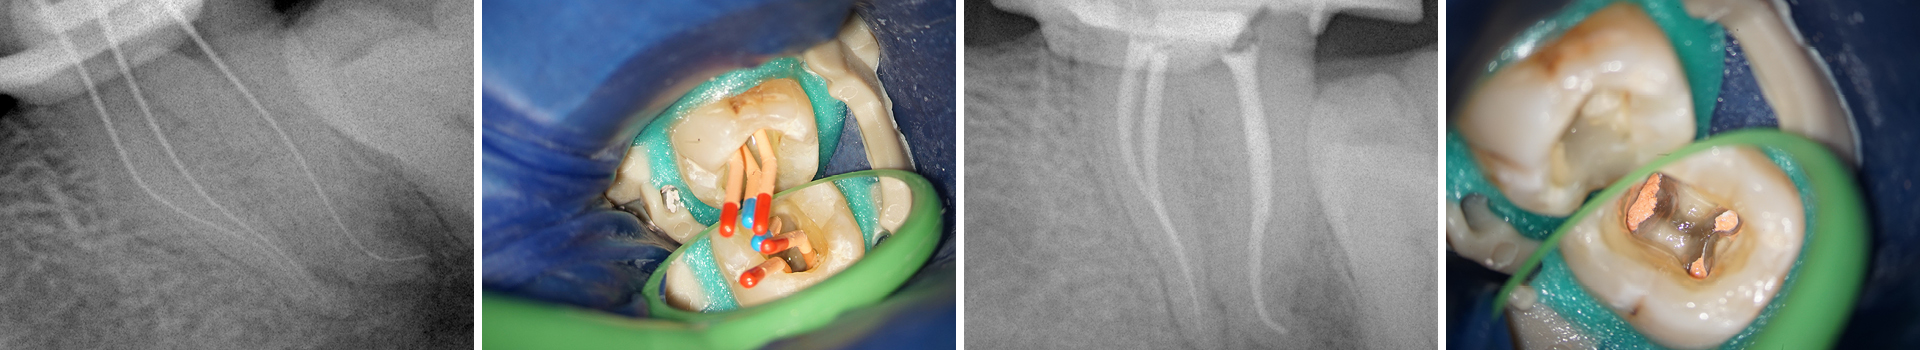

Abbildung 2

Röntgen-Messaufnahme: Aufgrund der Kanalkrümmung erfolgte die Messaufnahme bereits nach der Erstellung eines Gleitpfades bis ISO 10. Der mb und ml Kanal verfügen jeweils über ein separates Foramen.

Abbildung 11

Masterconeaufnahme.

Abbildung 12

Kontrollaufnahme nach Wurzelfüllung: Die Obturation erfolgte in der sog. Single Cone Technik mit einem Sealer auf Tricalciumsilikatbasis. Vergleicht man die Röntgenmess- mit der finalen Obturationsaufnahme, so konnte durch dieses beschriebene Vorgehen sowohl eine signifikante Transportion als auch eine Feilenfraktur vermieden und eine adäquate Obturation ohne Extrusion erzielt werden.